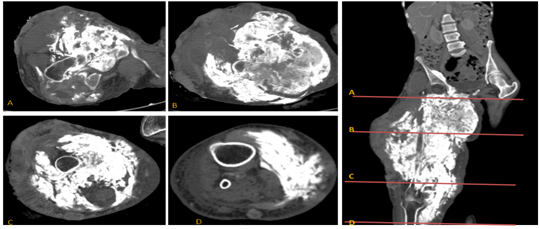

Figure 1 Extra-skeletal osteosarcoma of the thigh muscles.

Figure 3 MRI: large, heterogeneously calcified predominantly hypo dense tissue mass heterogeneously enhanced after contrast containing areas of liquefaction measuring 28x20x50 mm. This mass invades muscle, fat and skin tissue with bone lysis of the femoral bone in localized areas. Above it reaches the iliac psoas muscle and the right muscle of the right abdomen, sheathing the common homolateral femoral pedicle, which remains permeable. Below it reaches the anteromedial compartment of the right leg.

Figure 4 CT scan: (A-B) heterogeneous hyper dense mass in the thigh muscles. (C-D) Masses (blue arrow) intra parenchymal and sub pleural scattered in the 02 pulmonary fields with speculate contours-secondary locations.